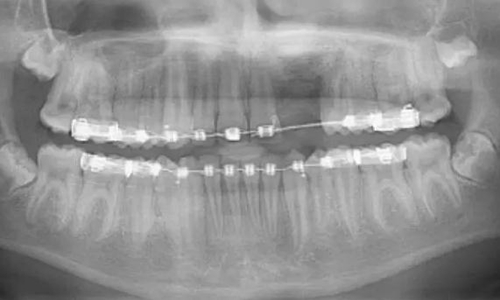

一名 23 區(qū)的9歲患者,在診所接受檢查時發(fā)現(xiàn)口內(nèi)中存在大范圍含牙囊腫[圖1]。由于上頜竇下沿出現(xiàn)大范圍突出,迫切需要接受囊腫去除手術(shù)[圖2和3]。

術(shù)前全景片[圖1]